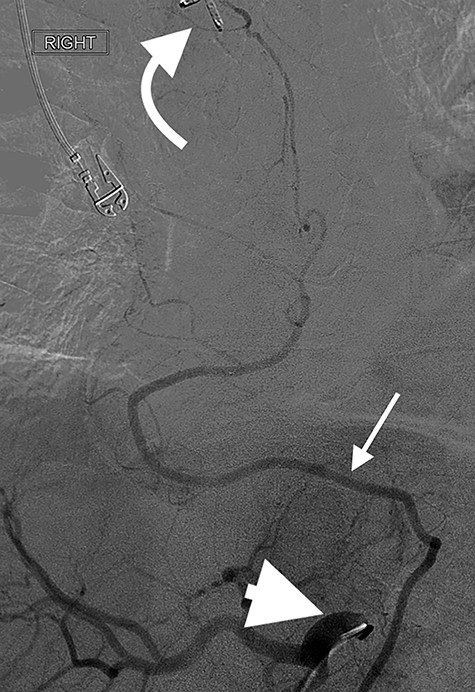

Successful coil embolization of the terminal portion of the gastro-epiploic arcade. Ellipse = coil.

Eight days later, he represented with an upper gastrointestinal bleed with massive haematemesis requiring immediate intubation for airway protection. Computer tomography angiography was unremarkable and an emergency gastroscopy revealed an extensive amount of blood and clot in the oesophagus and gastric conduit (limiting the view), but no active bleeding point. Conservative treatment in the Intensive Care Unit (ICU) with blood transfusion, proton pump inhibitors and life support were implemented. Another large bleed occurred 2 days later and a repeat gastroscopy revealed a non-bleeding visible vessel at the OG anastomosis and a haemostatic clip was applied. However, over the next 10 days, the patient remained blood transfusion dependent and had two further endoscopies. The first was unremarkable, but the second endoscopy re-demonstrated the luminal vessel at the OG anastomosis, with no evidence of the previously placed clip. This was felt to be the cause of his intermittent and problematic bleeding, so another haemostatic clip was attempted, resulting in pulsatile, moderate volume arterial bleeding. The procedure was abandoned and the patient transported immediately to the Interventional Radiology Suite. Right femoral access was obtained and angiography performed. The thoracic aorta was normal, so the celiac trunk was cannulated and angiography of the right gastro-epiploic artery performed (Fig. 1), revealing active extravasation of contrast at the OG anastomosis as shown in Fig. 2. A microcatheter was advanced along the length of the right gastro-epiploic artery to the OG anastomosis and coil embolization was performed (Fig. 3). Care had to be taken to ensure that the embolization was as distal as possible to limit the risk of ischaemic complications. The patient required lengthy ongoing care in the ICU for organ dysfunction but remained hemodynamically stable after embolization without evidence of conduit ischaemia. His hospital stay was obviously lengthy, but he was ultimately transferred to a rehabilitation unit.

Oesophagectomy is a major operation with significant perioperative morbidity. Respiratory and cardiac complications, along with gastric conduit ischemia and anastomotic leak, tend to dominate [3]. However, bleeding complications apart from those occurring intra-operatively are rarely reported [1, 2]. We present a unique case of an anastomotic bleed from a terminal branch of the gastro-epiploic vascular arcade. While the origin of this vascular arcade is a defined vessel (right gastric-epiploic artery) visible to the naked eye, the terminal portion is comprised of submucosal arterioles and capillaries and often devoid of a visible vessel [4]. However, as shown in Fig. 1, vascular supply to the terminal portion of the gastric conduit is present and can be abundant. The bleeding in this case likely occurred from incorporation in the anastomosis of either an invisible submucosal arteriole or the terminal portion of the right gastro-epiploic artery hidden within omental tissue. It is our standard practise to construct the OG anastomosis with the EEA circular stapler. It is common surgical knowledge that the oesophageal wall is thick [5] and has been our practise to use the 4.8-mm EEA staple height. There are several descriptions in the literature about this anastomotic technique and most recommend this staple height [6–8]. However, we believe that the higher staple height may have contributed to the bleeding issue in this case as there may have been insufficient compression of a submucosal arteriole. While it is impossible to be certain if a lower staple height would have prevented this situation, this case has resulted in our change to use the 3.5-mm EEA. In addition to this, we have become more meticulous in ensuring that the portion of the great curvature to be used for the anastomosis is cleared of excessive omental tissue to be sure no visible vessel is present that may get caught in the anastomosis.